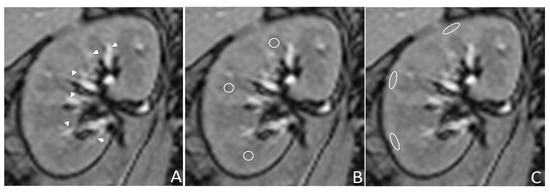

2.2. MRI Studies

2.3. Imaging Interpretation